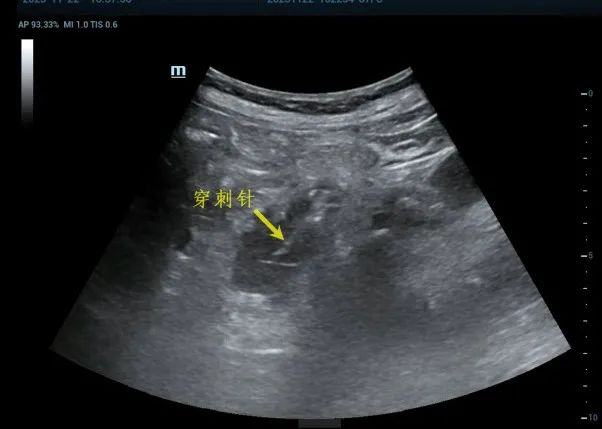

左侧肾上腺肿物穿刺活检

左肾上腺肿物 超声引导下穿刺活检